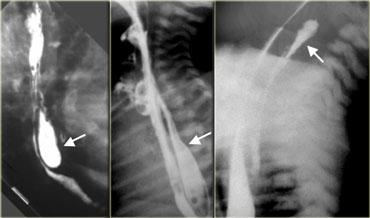

Túi thừa trên cơ hoành (Epiphrenic diverticulum)

Các túi thừa do áp lực này được phân loại dựa theo vị trí gần cơ hoành. /ul>

Nếu kích thước lớn, chúng có thể gây hẹp thực quản hoặc dẫn đến hít sặc.

Bên trái là một ví dụ khác về túi thừa trên cơ hoành.

CT cho thấy túi thừa kích thước lớn (mũi tên) lan sang phải, ngay trên cơ hoành.

Bệnh nhân này không có triệu chứng.

Túi thừa cửa sổ chủ-phổi (Aortopulmonary window diverticulum)

Thực quản bình thường có thể thoáng qua nhô vào cửa sổ chủ-phổi.

Nhô ra cố định là túi thừa không có ý nghĩa lâm sàng.

Bên trái là các túi thừa cửa sổ chủ-phổi nhỏ (mũi tên), là phát hiện tình cờ ở hai bệnh nhân.

Ngoài cùng bên trái là túi thừa do kéo (mũi tên) do bệnh u hạt vùng rốn phổi.

Hạch vôi hóa (dấu hoa thị).

Ở giữa là túi thừa do áp lực (mũi tên) do tăng áp lực trong lòng ống.

Bên phải là nhiều túi thừa do áp lực (mũi tên) xuất hiện trước khi thực hiện phẫu thuật cắt cơ Heller điều trị co thắt tâm vị (achalasia).

Bên trái là túi thừa do kéo (mũi tên) thứ phát sau lao hậu nguyên phát.

Hình ảnh này có thể nhầm lẫn với tổn thương phổi dạng hang trên phim X-quang ngực.

Túi thừa giả (pseudodiverticula) có thể gặp trong viêm thực quản trào ngược.

Bên trái là hình ảnh một bệnh nhân có thoát vị hoành, viêm thực quản trào ngược và túi thừa giả (mũi tên) tại vị trí hẹp đoạn gần.

Trái: Thủng do thủ thuật (mũi tên). GIỮA: Nang đôi thực quản có thông nối (mũi tên). PHẢI: Thoát thuốc do thủng hạ họng do thủ thuật ở trẻ sơ sinh

Một số tình trạng bệnh lý khác có thể bắt chước hình ảnh túi thừa.

Bên trái là hình ảnh hai bệnh nhân bị thủng do thủ thuật và một bệnh nhân có nang đôi thực quản dạng thông nối.